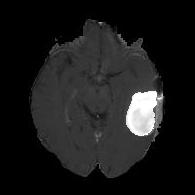

We argue that the sub-optimal paradigm of processing different abstractions within a single CNN pipeline can be remedied through the effective processing of information in a structured manner. Consequently, we devise strategies for disentangling the edge and texture information within a single training pipeline. Figure 2 illustrates how our proposed module, dubbed EG-CNN, can be paired with any existing CNN encoder-decoder to improve segmentation quality near intensity edges. We have applied our EG-CNN to the tasks of brain and liver tumor segmentation in medical images (Figure 3).

(1) Brain MR (2) Liver MR (3) Liver CT (4) Lung CT